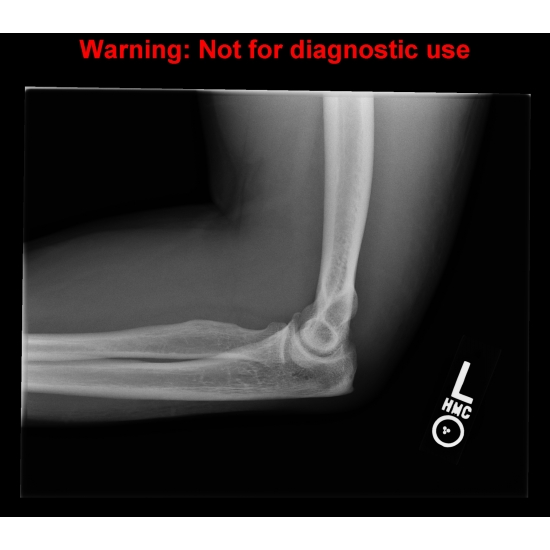

| Acute Bilateral Elbow Pain After A Fall - Page #3 | |||